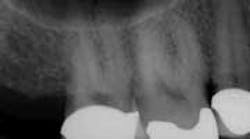

For example, in canal anatomy that appears to be fairly straight on preoperative radiographs in roots with traditional taper, a single file system such as WaveOne(Dentsply Tulsa Dental Specialties) would be an excellent choice to achieve cleanliness and shape (Figs. 1 and 2). The single-file reciprocating system would also have the added benefits of simplicity and efficiency.

In these three cases, different instrumentation systems were used to create the final shape of the root canal system. In spite of differences in the number of files used, the file design and file movement, the end results look very similar. Although potentially confusing to clinicians, the advances in metallurgy and file design allow for safer and more efficient cleaning and shaping of the root canal system than ever before. However, despite these advances, the success rates of endodontic treatment have stagnated over the last several decades, indicating there is more to clinical success than a dense, white line on a radiograph. Canal shaping is important, but it is paramount that an effective irrigation protocol is incorporated into the endodontic procedure to safely and effectively eliminate all possible bacteria.Fig. 1: Although access is usually an issue when treating second molars, the shape of the roots and good chamber size suggest WaveOne would be an ideal file system for tooth No. 2.

Fig. 2: Following establishment of a glide path and removing the dentin triangle, a single WaveOne primary file was used to create the final shape. This shape would allow for deep and safe delivery of irrigants and maximum disruption of biofilm.